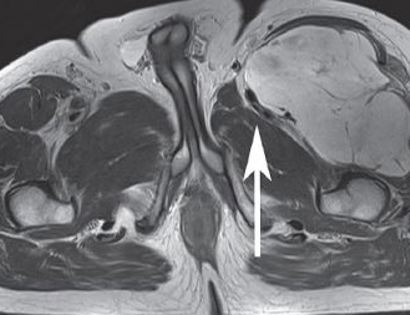

This MRI shows a large mass on the upper left hand side of the thigh (upper right hand side of the image) which is compressing the muscles and nerves.